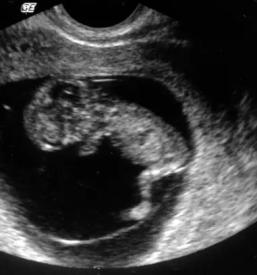

V naši ambulanti se vedno trudimo imeti čimbolj strokoven pristop. To lahko dosežemo le z nenehnim izobraževanjem in spremljanjem razvoja medicinskih postopkov doma ter v tujini. Tako smo se med drugim specializirali za različne preglede, kot je nuhalna svetlina Ptuj.